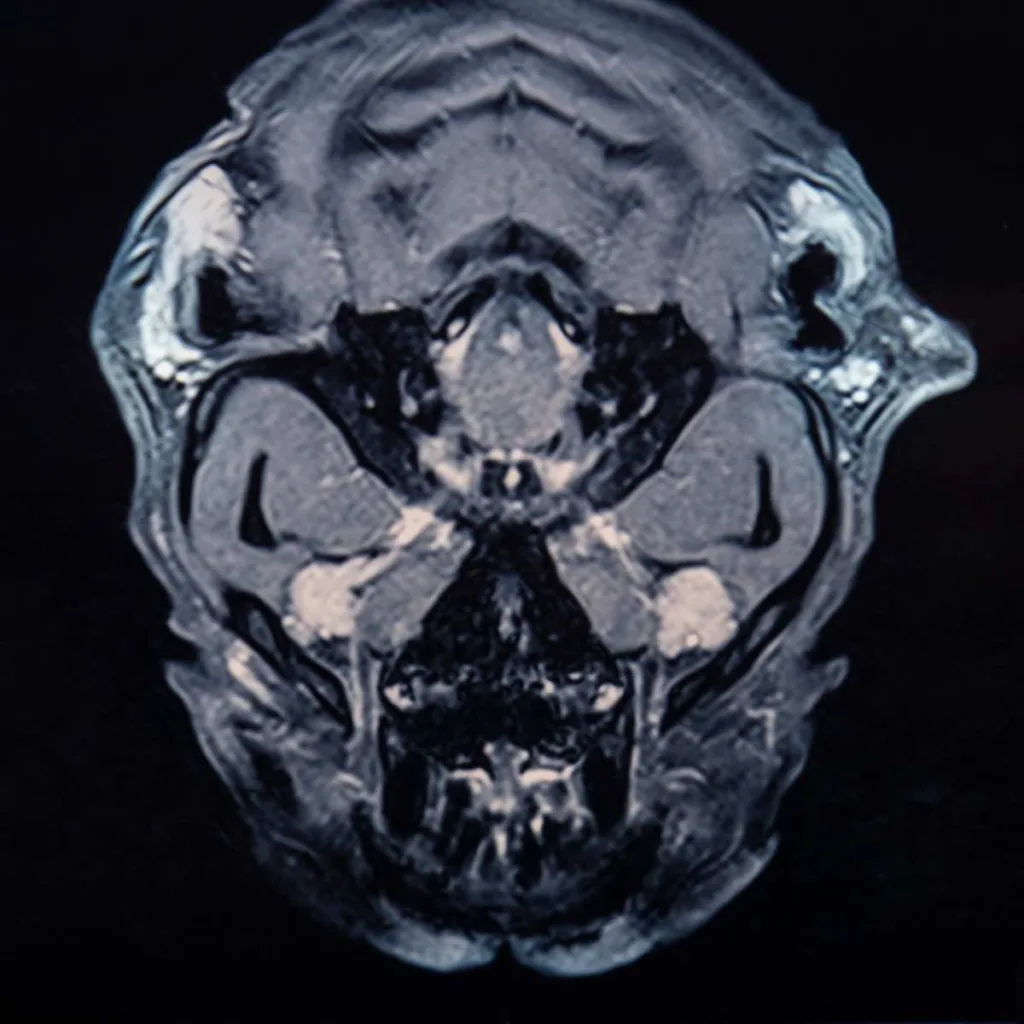

Resonancia Magnética de Cabeza